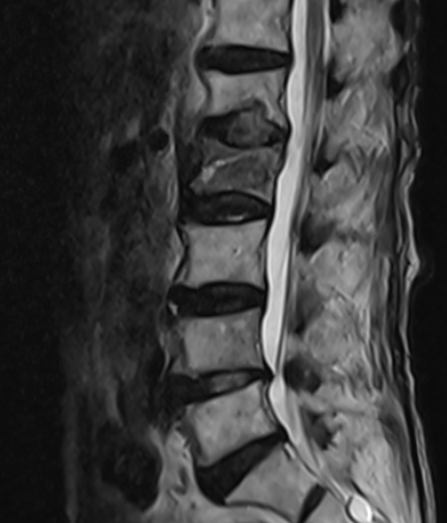

十余年来,我科室相继开展骨质疏松症的相关诊治工作,逐渐形成了自身的诊治体系,后经过整合联系,形成了以骨科二病区为龙头,联合检验科、放射科、内分泌科、血液风湿科等多学科结合、内外协作的骨松诊治MDT模式。目前采用的诊断方式有血钙及维生素ADKE检测、双能X线骨密度检测等,治疗方面也内外兼修,既可应用促成骨的四烯甲萘醌等,抑制骨吸收的唑来膦酸等药物治疗,又可采取椎体强化术、经皮穿刺椎弓根钉置入术等有效手术治疗,可结合患者自身情况,采取合适的治疗手段。开展骨质疏松诊治工作的十几年来,遵循指南,结合当地实际,总结归纳出了一套立足自身实际的诊疗体系,采取药物治疗与手术治疗相结合、因人而宜、综合施治的个体化的综合诊疗方案等。近年来,随着微创理念的推行和ERAS理念的实践,骨科二病区率先在本地区开创性的应用微创经椎间孔入路椎体强化术、经皮穿刺椎弓根钉置入术等先进治疗手段,实现立竿见影的治疗效果,深得广大患者的好评,取得了良好的社会效益和学术影响力,使桓台百姓足不出县即可享受到国内外先进的脊柱外科诊治体验。

术后术前